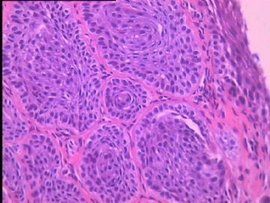

非典型鱗狀細胞非典型鱗狀上皮細胞指不能肯定其形態特徵及病變性質的形態異常的鱗狀上皮細胞.對此類患者應注意複查。複查前注意避免性生活和陰道的治療。是否有惡性病變可以結合進一步的宮頸活檢進行判斷。因其屬於癌前期病變,一定要嚴密觀察。由癌前期病變到浸潤癌的變化一般很慢,約需8-10年甚至20年。在癌前期階段,異常的細胞不侵犯間質,更不發生轉移,如果在這時發現,並給以相應治療,則治癒的機會是非常高的。但在宮頸癌已變為浸潤癌以後,則發展一般很快,如不經治療,病人可在2-5年內死亡。非典型增生可分為輕、中及重度,如不經治療約10-15%的輕及中度非典型增生可發展為浸潤癌,約75%的重度非典型增生及原位癌,可發展為浸潤癌。活檢如為輕度非典型增生者,暫按炎症處理,半年隨訪刮片和必要時再作活檢。病變持續不變者可繼續觀察。診斷為中度不典型增生者,應適用雷射、冷凍、電熨。對重度不典型增生,一般多主張行全子宮切除術。

非典型鱗狀細胞增生分為輕、中、重度,輕度大部分(百分之60)可逆轉,中、重度為癌前病變,其實重度就可以歸為原位癌了。非典型鱗狀細胞是指不能肯定形態特徵及病變性質的形態異常的鱗狀上皮細胞,是細胞病理學診斷判斷依據,提示為癌前病變,應該定期複查以確認。如是非典型鱗狀細胞增生,說明細胞具有異型性。